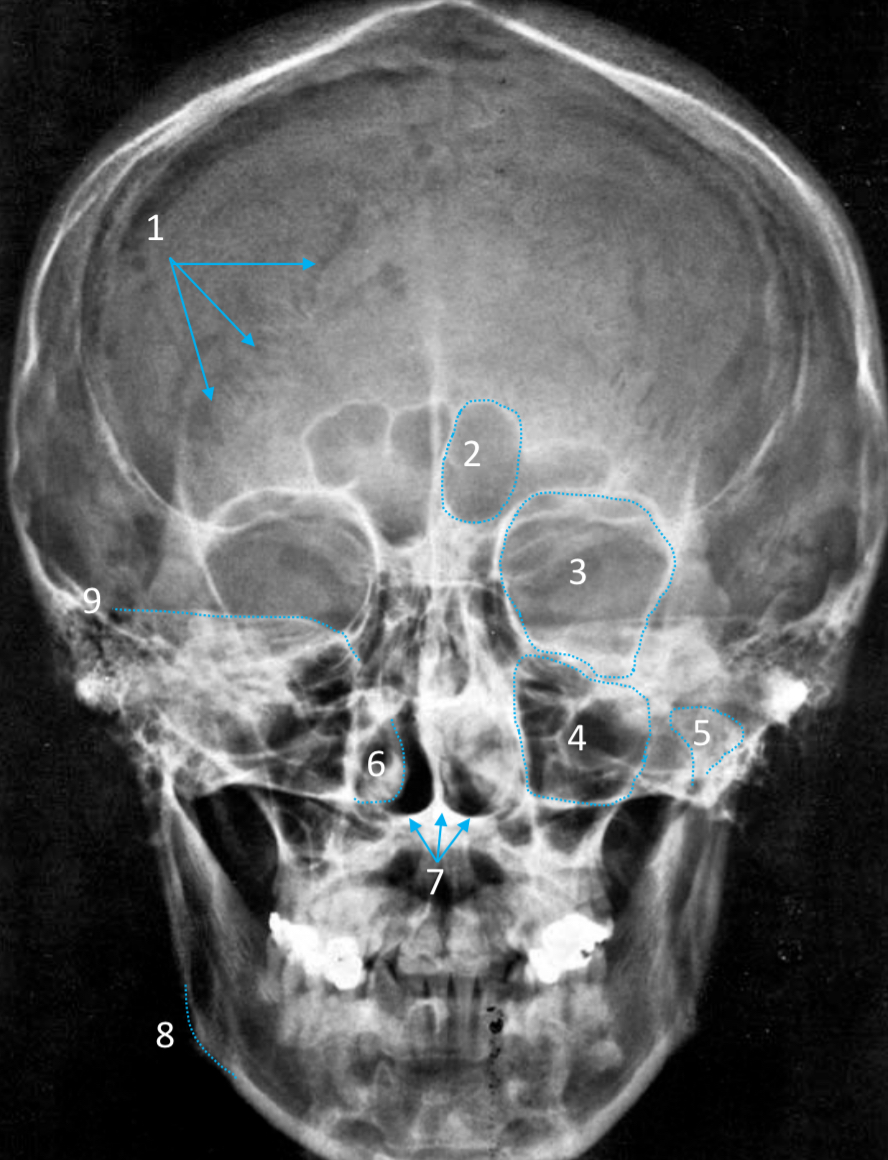

Frontal sinus

ID structure

Pituitary fossa

ID structure

Frontal sinus

ID structure

Orbital margin

Orbit

Maxillary sinus

ID structure

Mandibular condyle

ID structure

Inferior nasal concha

ID structure

Hard palate

ID strucutre

Gonial angle

ID strucutre

Petrous ridge

ID structure

Groove of middle meningeal a.

ID structure

Roof of orbit

ID structure

Frontal sinus

ID structure

Pituitary fossa

ID structure

Petrous ridge

ID structure

Sphenoid sinus

ID structure

Hard palate

ID structure

Mastoid air cells

ID structure

Zygomatic arch

ID structure

Mandibular condyle

ID structure

External auditory meatus

ID structure

Mastoid air cells

ID structure

Foramen magnum

ID structure

Foramen ovale

ID structure

Foramen spinosum

ID structure